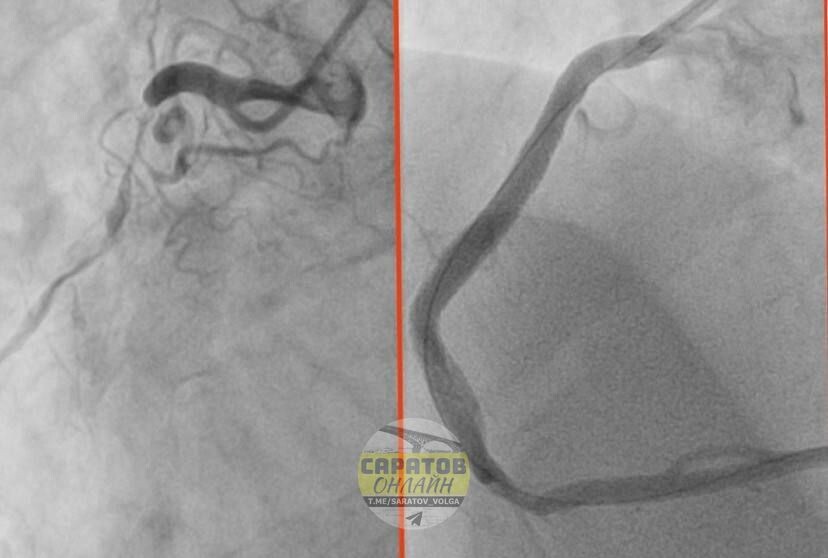

«Результаты суточного мониторирования по Холтеру потребовали экстренной помощи. При выполнении коронарографии врачи были шокированы: сужение просвета коронарной артерии достигло 90%! Кровь почти перестала поступать к сердцу», - рассказали сотрудники БГКБ в телеграм-канале.

Состояние сосудов 32-летнего мужчины специалисты сравнили с изменениями, характерными для глубокой старости: были поражены все три коронарные артерии. Чтобы предотвратить инфаркт, врачи приняли решение об экстренной операции.

В результате 3 марта пациенту провели стентирование. Кровоток удалось полностью восстановить. В настоящий момент состояние мужчины стабильно, его ждет реабилитация.